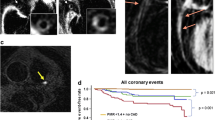

Another method for imaging calcium is positron emission tomography (PET) using 18F-labeled sodium fluoride (NaF). This tracer is deposited by chemisorptions onto hydroxyapatite and is used in oncology to identify sclerotic bone metastasis. Recent evidence suggests that it is not equivalent to CACS imaging [30] but that it can identify “spotty” calcification in the plaques thought to promote plaque vulnerability. In fact, results from one study indicate that NaF PET can identify culprit and ruptured plaques in patients with recent myocardial infarction [31•].

Anatomical Coronary Plaque Imaging

Coronary angiography by CT (CCTA) is a non-invasive method using intravenous contrast, typically to assess luminal stenoses. However, it has been shown that CCTA can also provide images of the vessel wall, and thus plaque characteristics, including positive remodeling, densitometry, and calcification [32]. With improved resolution, even small plaques that are not flow-limiting may potentially be assessed for vulnerability characteristics, although the spatial resolution remains a limitation for direct identification of vulnerable plaques [32]. Another challenge for CCTA is the fact that atherosclerosis is a systemic disease typically involving large parts of the coronary arteries. A comprehensive evaluation of coronary plaque morphology by visual evaluation is a cumbersome task. Multisequence magnetic resonance imaging (MRI) is also able to image the coronary artery wall and plaque morphology [33]., This method is even more technically challenging, however, due to cardiac and respiratory motion of the often small tortuous vessels. MRI does appear to be useful for imaging the larger carotid and aortic plaques.

An important advantage of myocardial perfusion imaging is that it is a functional method of imaging perfusion at the myocyte level and thus can determine whether a borderline epicardial stenosis causes a significant change in perfusion. One study (n = 111) on the association between PAD and subclinical CAD combined anatomical (CCTA) and ischemia (stress MRI) imaging [28••]. Of 80 patients with plaques on the CCTA (40 with significant and 40 with non-significant stenosis), only 10 were found to have ischemia on subsequent stress MRI.

Metabolic Imaging of the Vulnerable Plaque

PET imaging of atherosclerosis has thus far focused primarily on fluorine-18-fluorodeoxyglucose (18F-FDG). The molecule is a glucose analogue that accumulates in metabolically active cells such as macrophages. The first report on 18F-FDG accumulation in the large arteries emerged in 2001 [37], and since then, a large body of evidence has materialized linking FDG uptake to the macrophage contents of high-risk plaques [38–40]. This observation is in line with the emerging consensus of atherosclerosis as an inflammatory disease. A major drawback of imaging coronary atherosclerosis with FDG-PET, however, is the lack of specificity of the tracer, and another limitation is the high uptake of FDG in the myocardium, which produces a suboptimal signal-to-noise ratio. Consequently, in contrast to FDG imaging of carotid plaques, few studies have utilized FDG-PET to image coronary atherosclerosis [41•, 42]. One recent retrospective study indicated a potential future role of arterial FDG-PET in risk stratification of asymptomatic patients. The authors retrospectively identified 513 FDG-PET examinations and revealed a predictive value of arterial FDG uptake for subsequent cardiovascular events in asymptomatic individuals [43].

Hybrid imaging combining anatomical information from a CCTA with metabolic or molecular information from PET imaging may represent a valuable non-invasive modality for the identification of significant microvascular disease and flow-limiting epicardial coronary artery lesions, as well as for demonstration of the characteristics of the vulnerable plaque in selected patients with PAD.

Clinical integrated PET/MRI systems have recently been introduced. MRI can effectively characterize plaque morphology (e.g., hemorrhage and the lipid-rich necrotic core), and the combination with PET-derived molecular imaging holds great potential for in vivo identification of vulnerable plaques. The limited availability of the PET/MRI imaging systems and expensive production of specific PET tracers, however, will likely restrict such a technique to experimental use for some time. Thus far, few reports have been published on hybrid imaging for the study of atherosclerosis [53•], and none have used it for coronary artery imaging. One study combined CACS with CCTA and MRI to identify high-risk PAD patients, but the image selection protocol itself was not validated in the trial [28••].